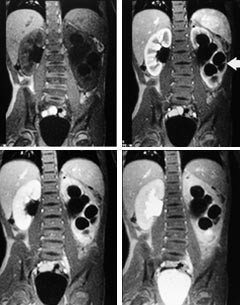

Tumorer med innvekst til sentralnervesystemet, for eksempel fra øre-nese-hals-området, kan nøyaktig kartlegges med MR, og operabilitet kan vurderes enklere og sikrere enn ved CT med aksiale snitt (fig 3). Ved å kombinere MR med ultralydveiledet biopsi og beinmargsprøver, samt ev. CT i samme seanse, spares barnet for flere narkoser. En slik integrering av MR-undersøkelse i utredningsrekken blir stadig oftere etterspurt hos barn.

Nevroblastom er et meget godt eksempel på en tumorform som med fordel kan utredes og følges med MR (fig 4). Ved paravertebral lokalisasjon av tumor skal kartleggingen utføres med MR på grunn av tendensen til innvekst i spinalkanalen gjennom foramen intervertebrale. Intraspinal utbredelse er ikke alltid forbundet med nevrologiske funn, men det kan være avgjørende for valg av behandling å vite om tumors primære utbredning, og MR vil på den enkleste og beste måten gi denne informasjonen. Forkalkninger i tumor sees imidlertid bedre med CT enn med MR.